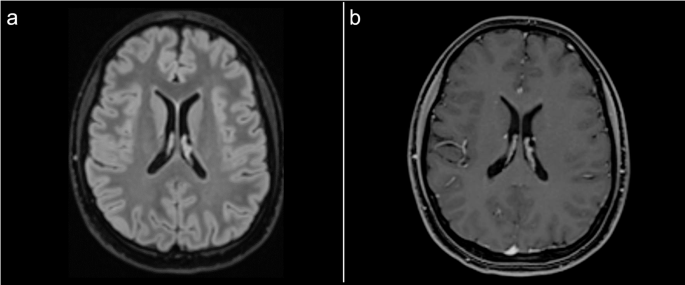

入院第6天开始使用静脉注射甲基泼尼松龙(1克/天)治疗,持续7天。入院第9天,患者临床症状有所改善,出院时症状持续缓解。1个月随访时,MRI显示T2/FLAIR高信号灶和增强灶几乎完全消失(图2),随后开始使用硫唑嘌呤作为维持治疗。1年随访时,未出现临床或MRI复发。

接受7天皮质类固醇治疗后的1个月随访脑部MRI:a面板显示液体衰减反转恢复序列,显示左侧壳核-脑豆状核区域的高信号灶几乎完全消失;b面板显示增强后T1加权序列,显示左侧壳核-脑豆状核区域的钆增强灶消失。